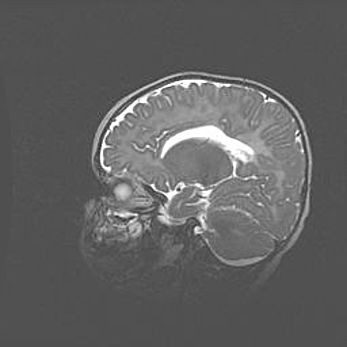

Неполная лизэнцефалия (пахигирия). Открытая гидроцефалия.

Возраст: 17 дней

Вес: 3110 г

Пол: мужской

Окружность головы: 33,5 см

Срок гестации: 35-36 недель

Лизэнцефалия—недоразвитие корковой пластинки и мозговых извилин в результате нарушения миграции нейронов коры. Поверхность мозговых полушарий гладкая. Микроскопически выявляется отсутствие нормальных слоев коры и скопление групп нейронов в подкорковом белом веществе.

Пахигирия—уменьшение числа вторичных извилин. В пораженном полушарии нервные клетки образуют толстый недифференцированный слой с неправильно расположенными нервными волокнами и группами гетеротопных клеток. Нервные клетки незрелые. Белое вещество истончено. При этом нередко аномально развит корково-спинномозговой путь.